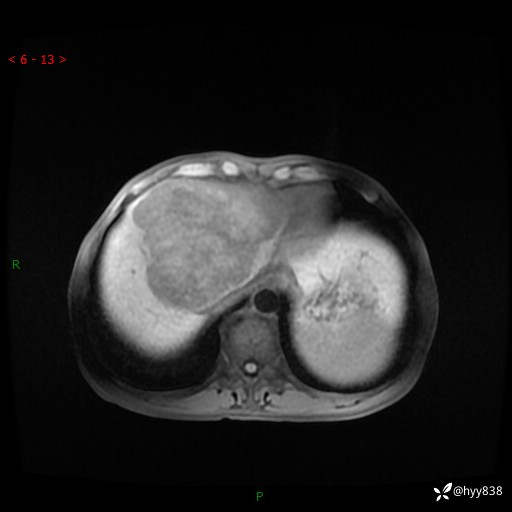

【患者信息】:58岁/男

【主诉】:发现肝占位2天

【现病史及既往史】:患者2天前于当地市第五医院查上腹部磁共振提示:肝脏S4段占位性病变,肝ca可能,胆囊结石,腹膜后多发肿大淋巴结,无剑突下及右上腹疼痛不适,无明显反酸、嗳气,无畏寒、头晕、头痛,无尿频、尿急、尿痛等不适,今为求进一步治疗特来我院就诊,门诊以“肝占位”收住我科。 患者病程中精神、睡眠、饮食尚可,大小便正常、体力体重无明显变化

【检查】:肝脏MRI】平扫+增强